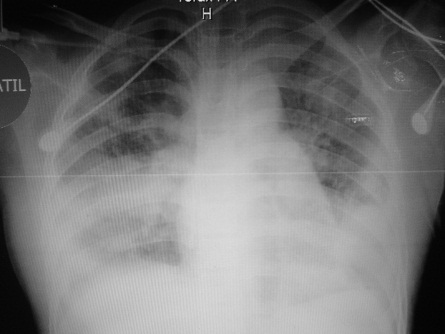

El amplio espectro clínico de la neumonía adquirida en comunidad genera problemas para su diagnóstico. La neumonía producida por Staphylococcus aureus es conocida como necrotizante, de rápida evolución y alta mortalidad. Se describe el caso de una mujer de 14 años con neumonía necrotizante por S. aureus resistente, evolucionó rápidamente a insuficiencia respiratoria requirió ventilación mecánica presento bacteriemia, empiema, neumatoceles, neumotórax bilateral persistente con fistulas broncopleurales que requirieron corrección quirúrgica. No se detectaron factores de riesgo. Los cultivos en sangre, líquido pleural, lavado traqueal fueron positivos y el tratamiento fue exitoso.